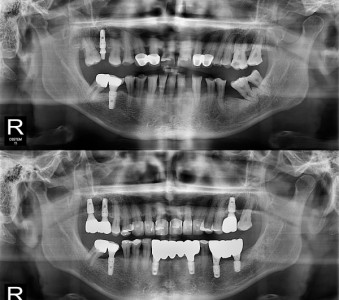

以成果证明实力。

国际摩牙齿科

真实临床案例